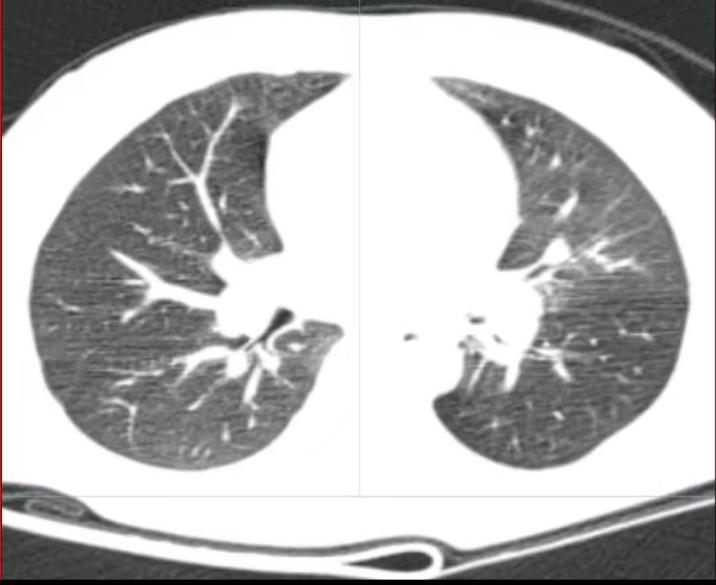

患儿,男,1岁11月,主因“咳嗽伴喘息4天”入院,患儿在4天前因吃“瓜子”时出现剧烈呛咳,伴喘息。入院前行胸部CT检查提示:1.左肺下叶主支气管异物可疑,建议行支气管镜检查;2.左肺上叶舌段支气管管腔变窄。